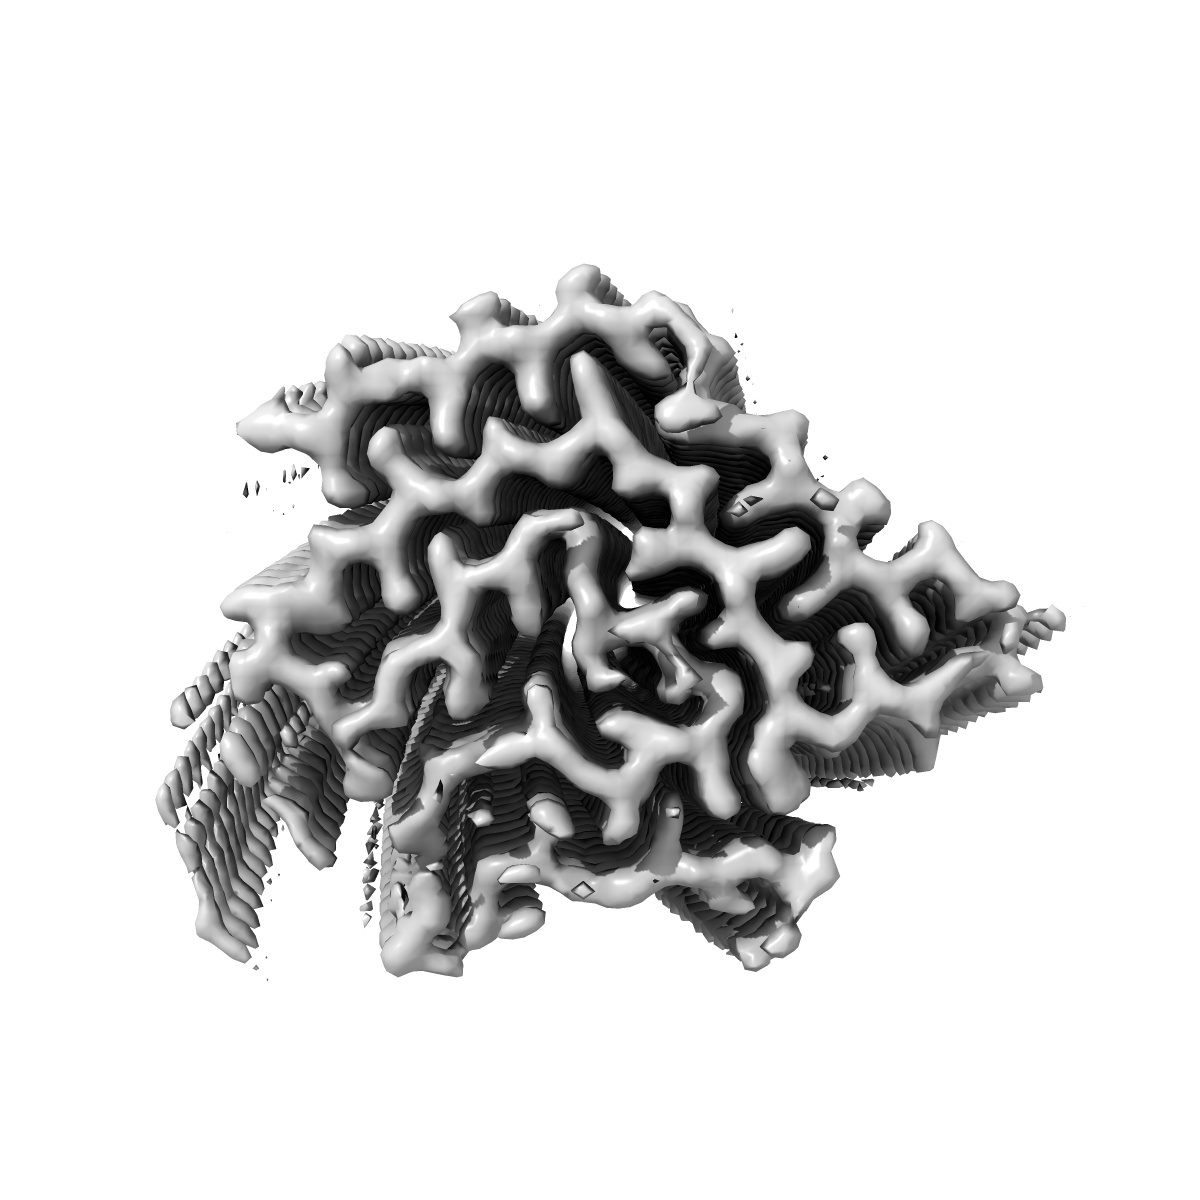

Helical reconstruction

2.68 Å

Structure of TDP-43 amyloid filament from type A FTLD-TDP (variant 3)

Sample: TDP-43 amyloid filaments extracted from the frontal cortex of an individual with type A FTLD-TDP

TDP-43 forms amyloid filaments with a distinct fold in type A FTLD-TDP.

Arseni D , Chen R, Murzin AG, Peak-Chew SY , Garringer HJ , Newell KL, Kametani F , Robinson AC , Vidal R , Ghetti B , Hasegawa M , Ryskeldi-Falcon B

(2023) Nature , 620 , 898 - 903